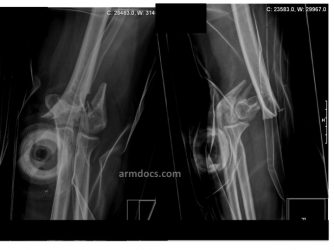

Distal humerus fracture